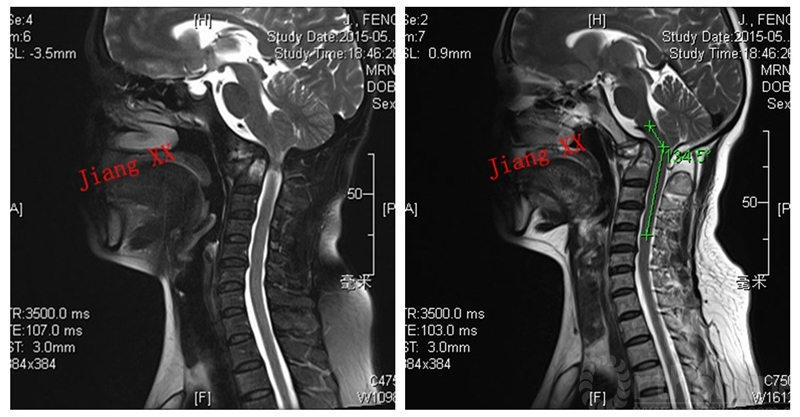

病例一:患者女性,49岁,因颈部活动受限4月入院,诊断为寰枢椎脱位,颅底凹陷。

术前MRI